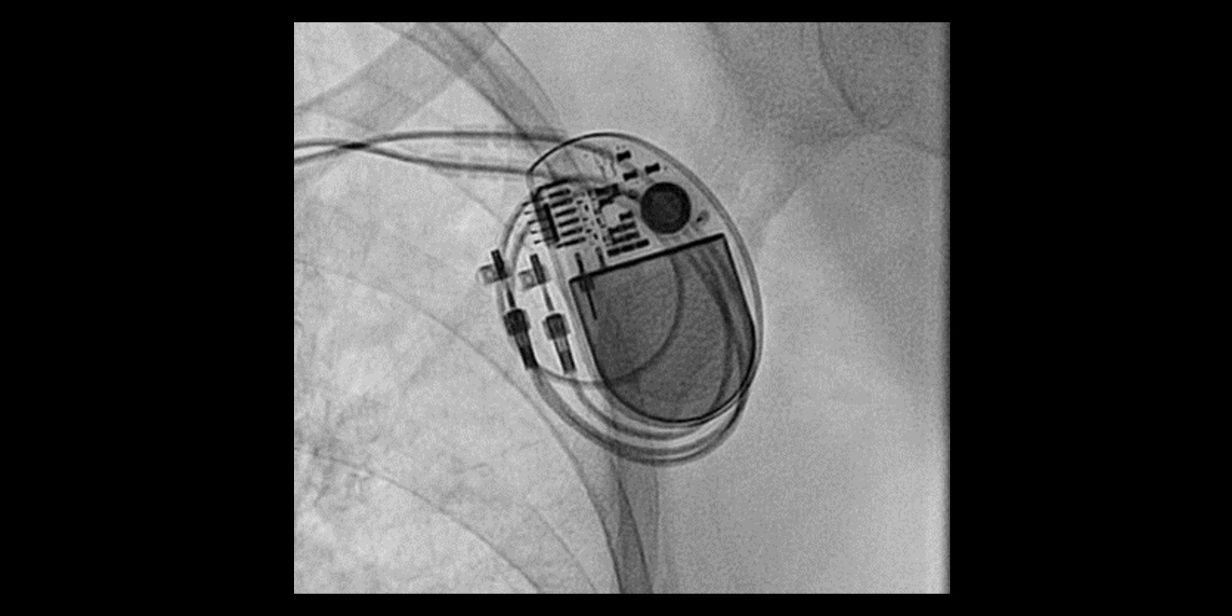

Unterschiede zwischen Schrittmacher und Defibrillator in Zeiten von Cardiac Rhythm Management Üblicherweise werden Herzfrequenzen unter 60/Minute als gering bradykard und unter 40/Minute als stark bradykard angesehen. Bradykarde Phasen des Herzschlags können Schrittmacher sind externe oder interne, implantierbare Systeme zur antibradykarden Therapie. Sie bestehen immer aus einem Aggregat und Sonden, die die

Bradykarde Herzrhythmusstörungen verursachen Symptome wie Synkope, Schwindel und Belastungsintoleranz und führen in Deutschland jährlich zur Implantation von mehr als 100 000

Bradykarde Herzrhythmusstörungen HRST mit Herzfrequenzen <60/min werden den bradykarden Herzrhythmusstörungen zugeordnet. Hierbei sollte die genaue Grenze immer Mit einem Herzschrittmacher werden langsame Herzrhythmusstörungen behandelt. Die Deutsche Herzstiftung informiert über die Therapie, den Eingriff und das Leben mit einem Herzschrittmacher.